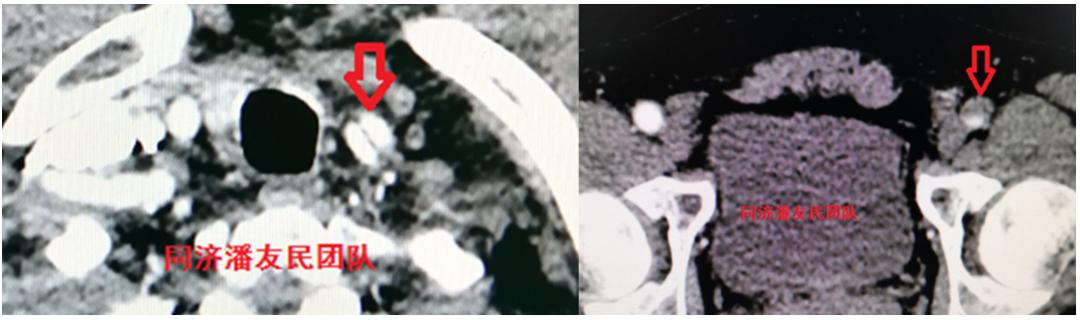

出院前复查主动脉CTA(图10)显示杂交手术重建弓部分支血管正常(左颈总动脉仍不显影)。